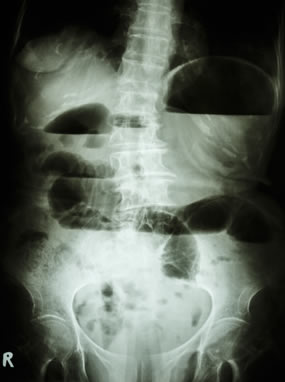

Οι απλές ακτινογραφίες κοιλίας αποτελούν την πιο σημαντική διαγνωστική δοκιμασία στον ειλεό. Πρέπει να γίνονται σε όρθια και σε ύπτια θέση. Αναδεικνύονται διατεταμένες έλικες λεπτού εντέρου (ημισεληνοειδείς διαυγάσεις) σε διάταξη κλίμακας στην ύπτια ακτινογραφία και υδραερικά επίπεδα, τα οποία είναι εμφανή στην απεικόνιση σε όρθια θέση.

Ακτινογραφία σε όρθια θέση

Αυτά τα ευρήματα μπορεί να είναι ελάχιστα ή και απόντα στην πρώϊμη φάση της απόφραξης, στην εγγύς απόφραξη, την απόφραξη «κλειστής έλικας», ιδιαίτερα σε ισχαιμική περίσφιξη της τελευταίας, και σε περιπτώσεις που οι έλικες είναι γεμάτες με πολύ εντερικό υγρό και περιέχουν λίγο αέρα. Σε απόφραξη πέραν του 24ωρου, ο αέρας και τα κόπρανα έχουν κενωθεί από το παχύ έντερο, και αυτό φαίνεται στην απλή ακτινογραφία. Στην πρώϊμη φάση ωστόσο, αλλά και στις περιπτώσεις που η απόφραξη είναι μερική και ο ειλεός ατελής, κάποια ποσότητα αέρα ανευρίσκεται στο παχύ έντερο, και αυτό αποτελεί ένα από τα στοιχεία που διαχωρίζουν τον πλήρη από τον ατελή ειλεό.